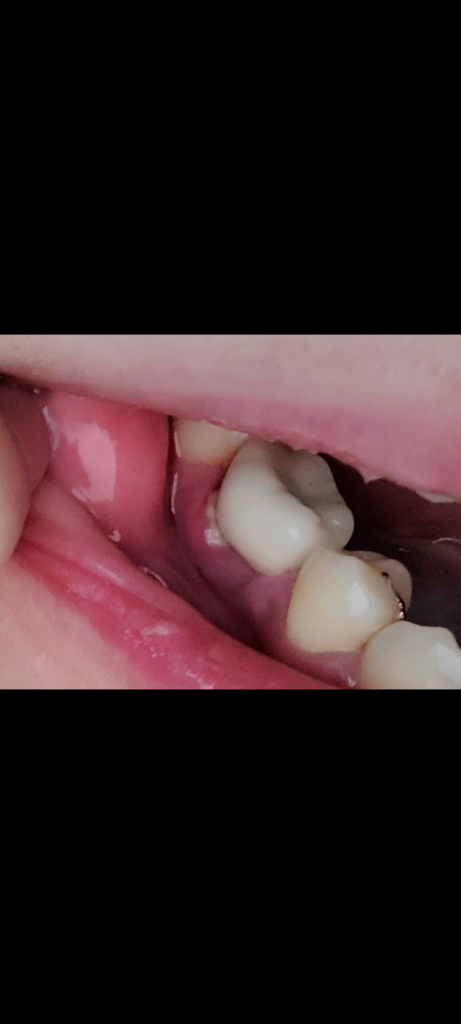

잇몸에 하얀 염증?같은게 생겼어요

임플란트 치아 쪽 잇몸에 생긴지 4~5일 정도 됐습니다.

2주전 스케일링했고 그 이후 구강세정기를 매일 썼고 최근 얼굴마사지 한다고 그쪽 부위를 좀 세게 문지르긴 했어요..

하얀게 처음보다 조금 커졌는데 치과를 가봐야할까요? 약국에서 약 사서 바르면 괜찮아질까요?

• 1번 째 사진